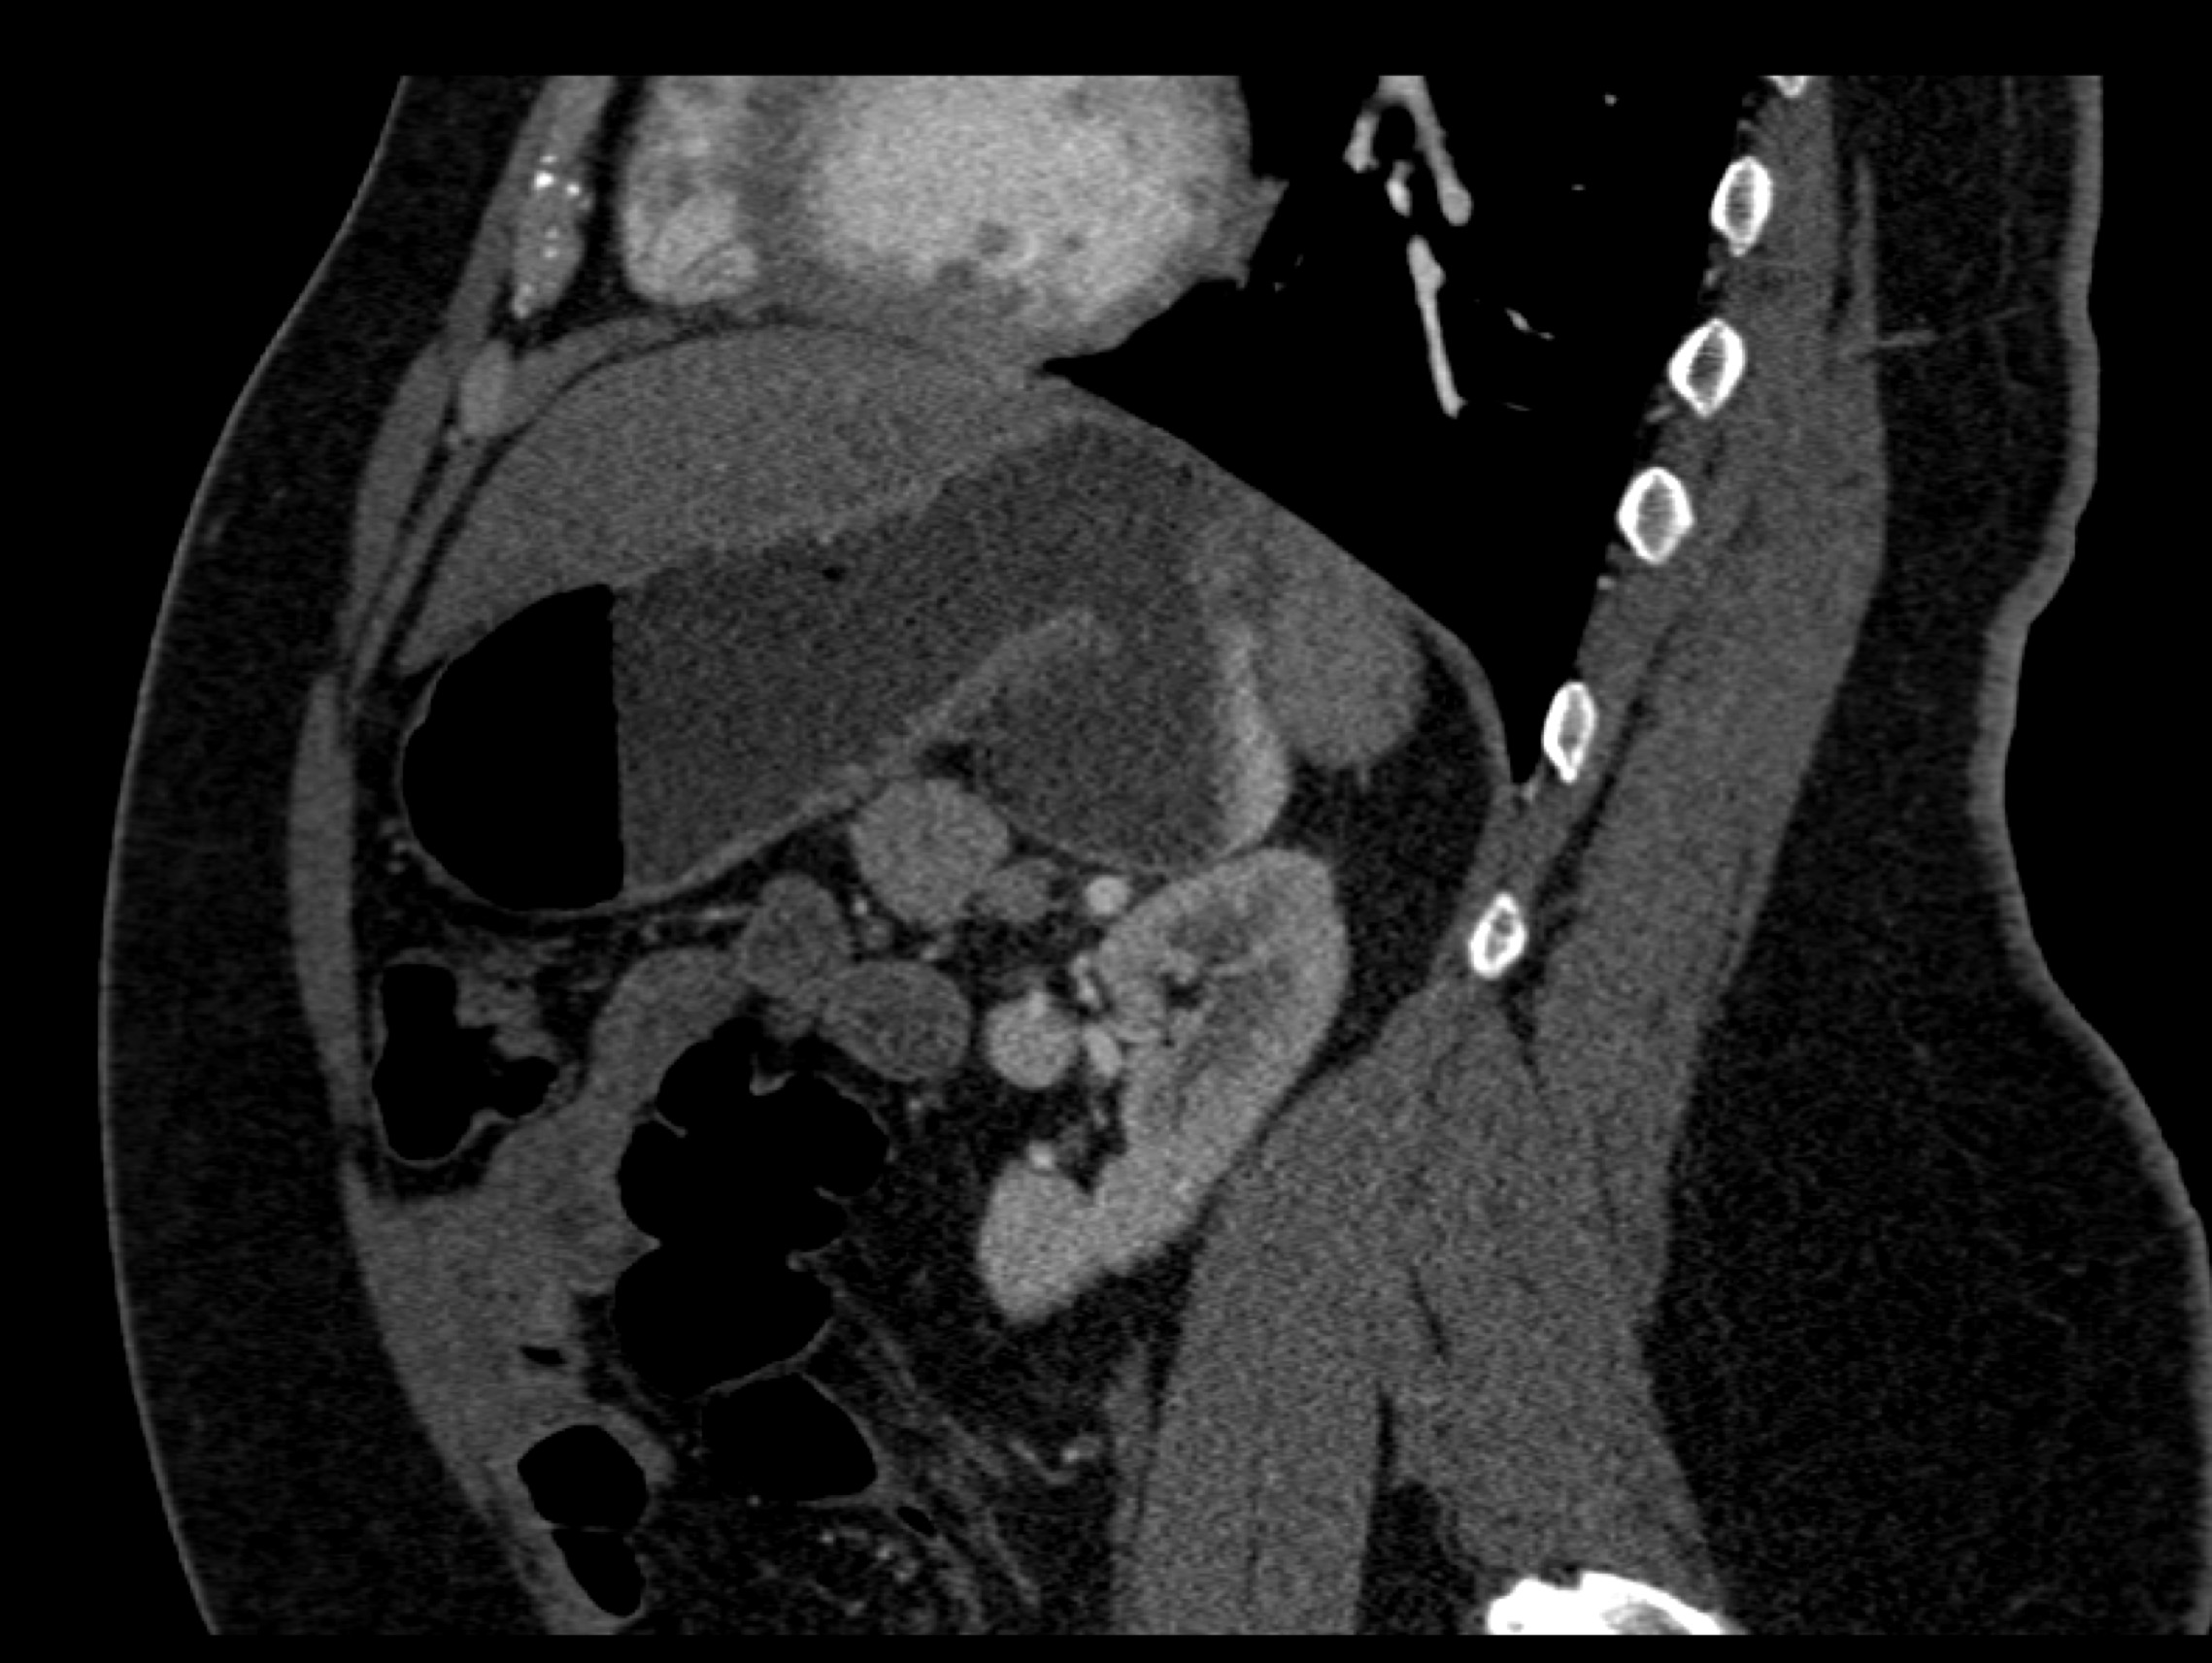

8) In this patient with RUQ pain and no history of trauma the best diagnosis is?

multiple hemangiomas

focal nodular hyperplasia

hepatic adenomas

angiosarcoma of the liver